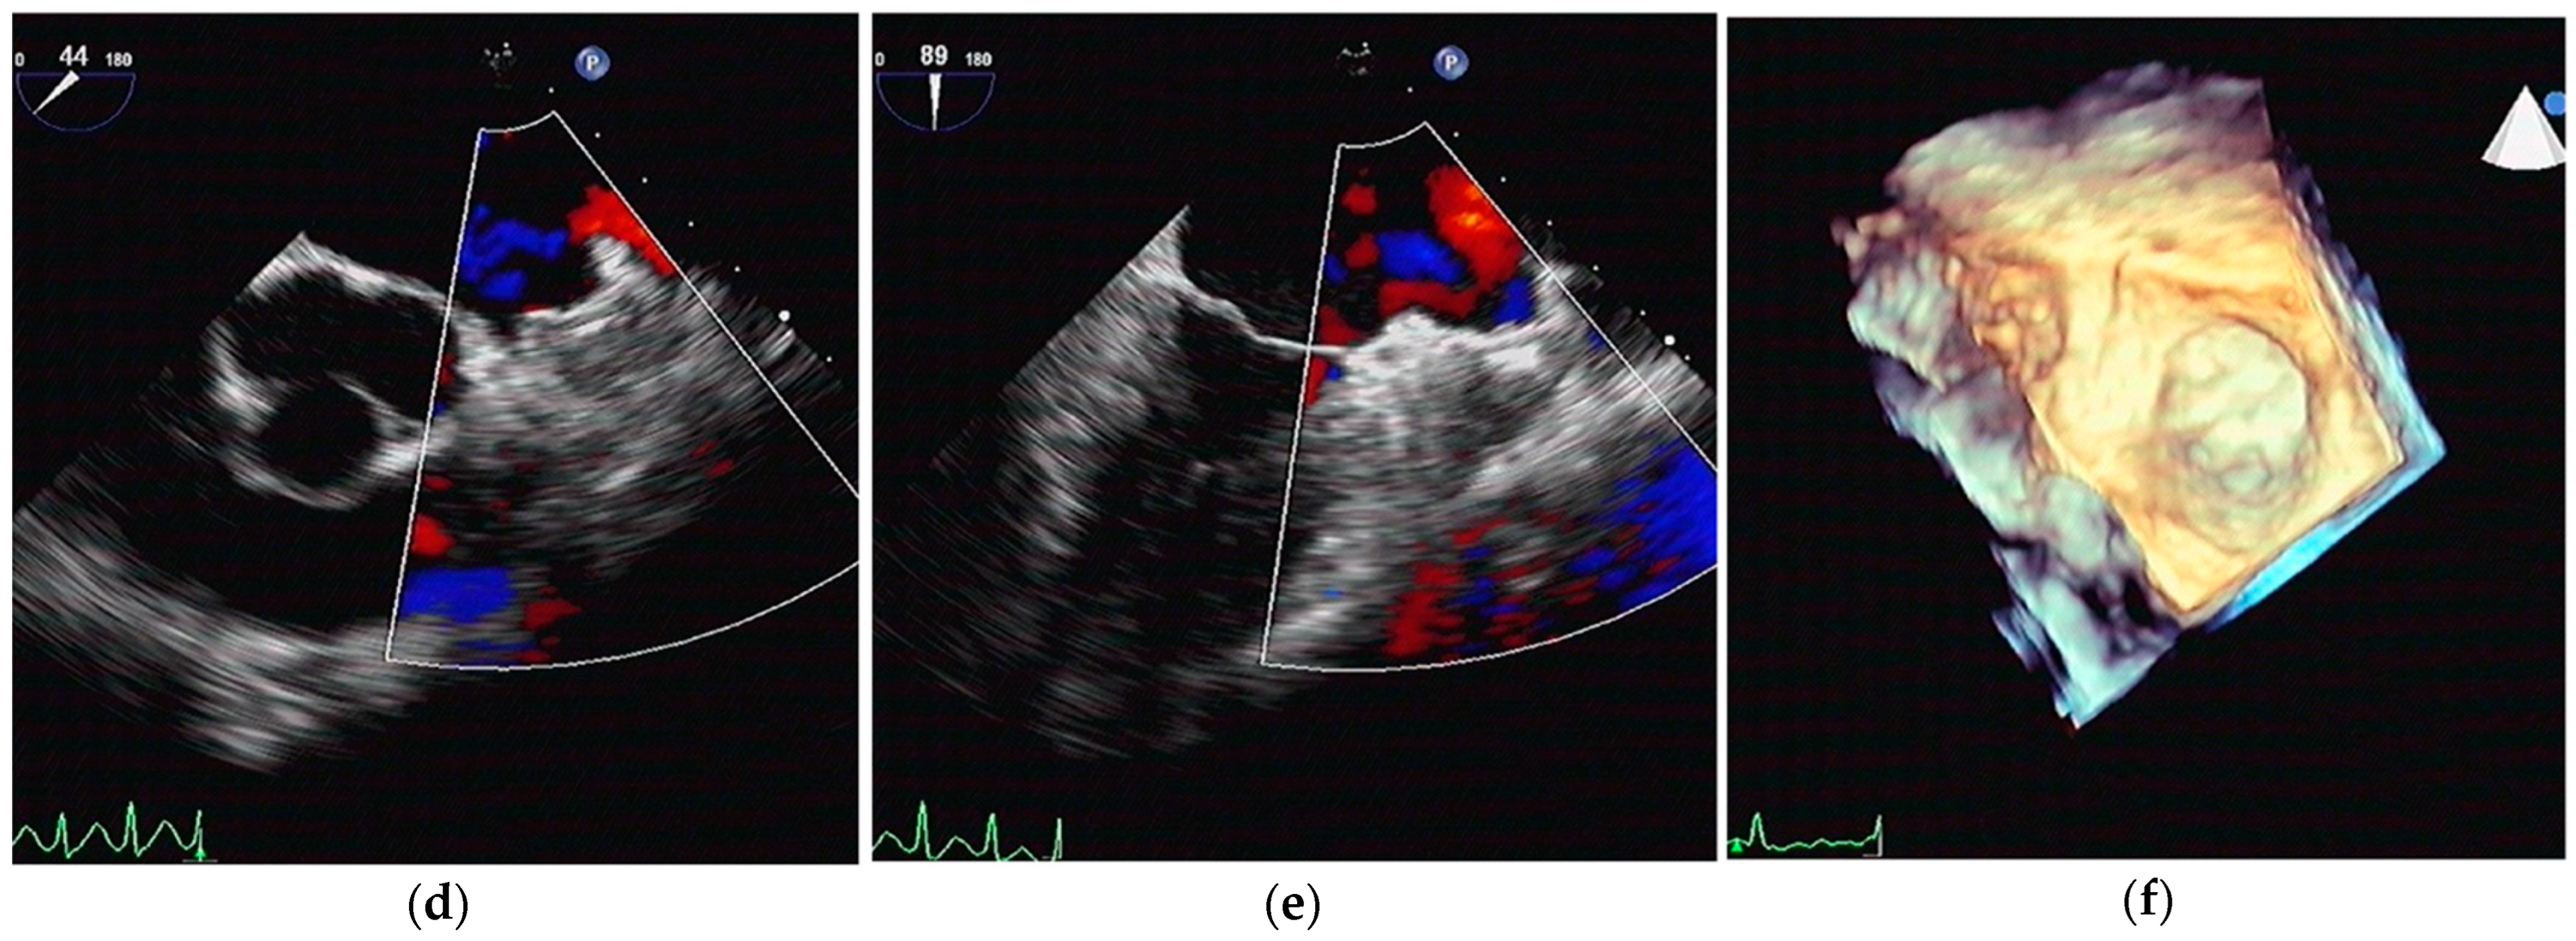

2.2. LA CA Procedure

3.2. Periprocedural Data

3.3. Follow-Up Results